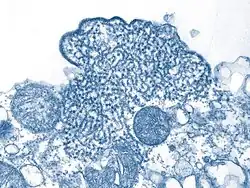

The Nipah virus (NiV) is a type of RNA virus in the genus Henipavirus, which normally circulates among fruit bats of the genus Pteropus.[7] Spread typically requires direct contact with an infected source; it can both spread between people and from other animals to people. Diagnosis is based on symptoms and confirmed by laboratory testing.[2][1]